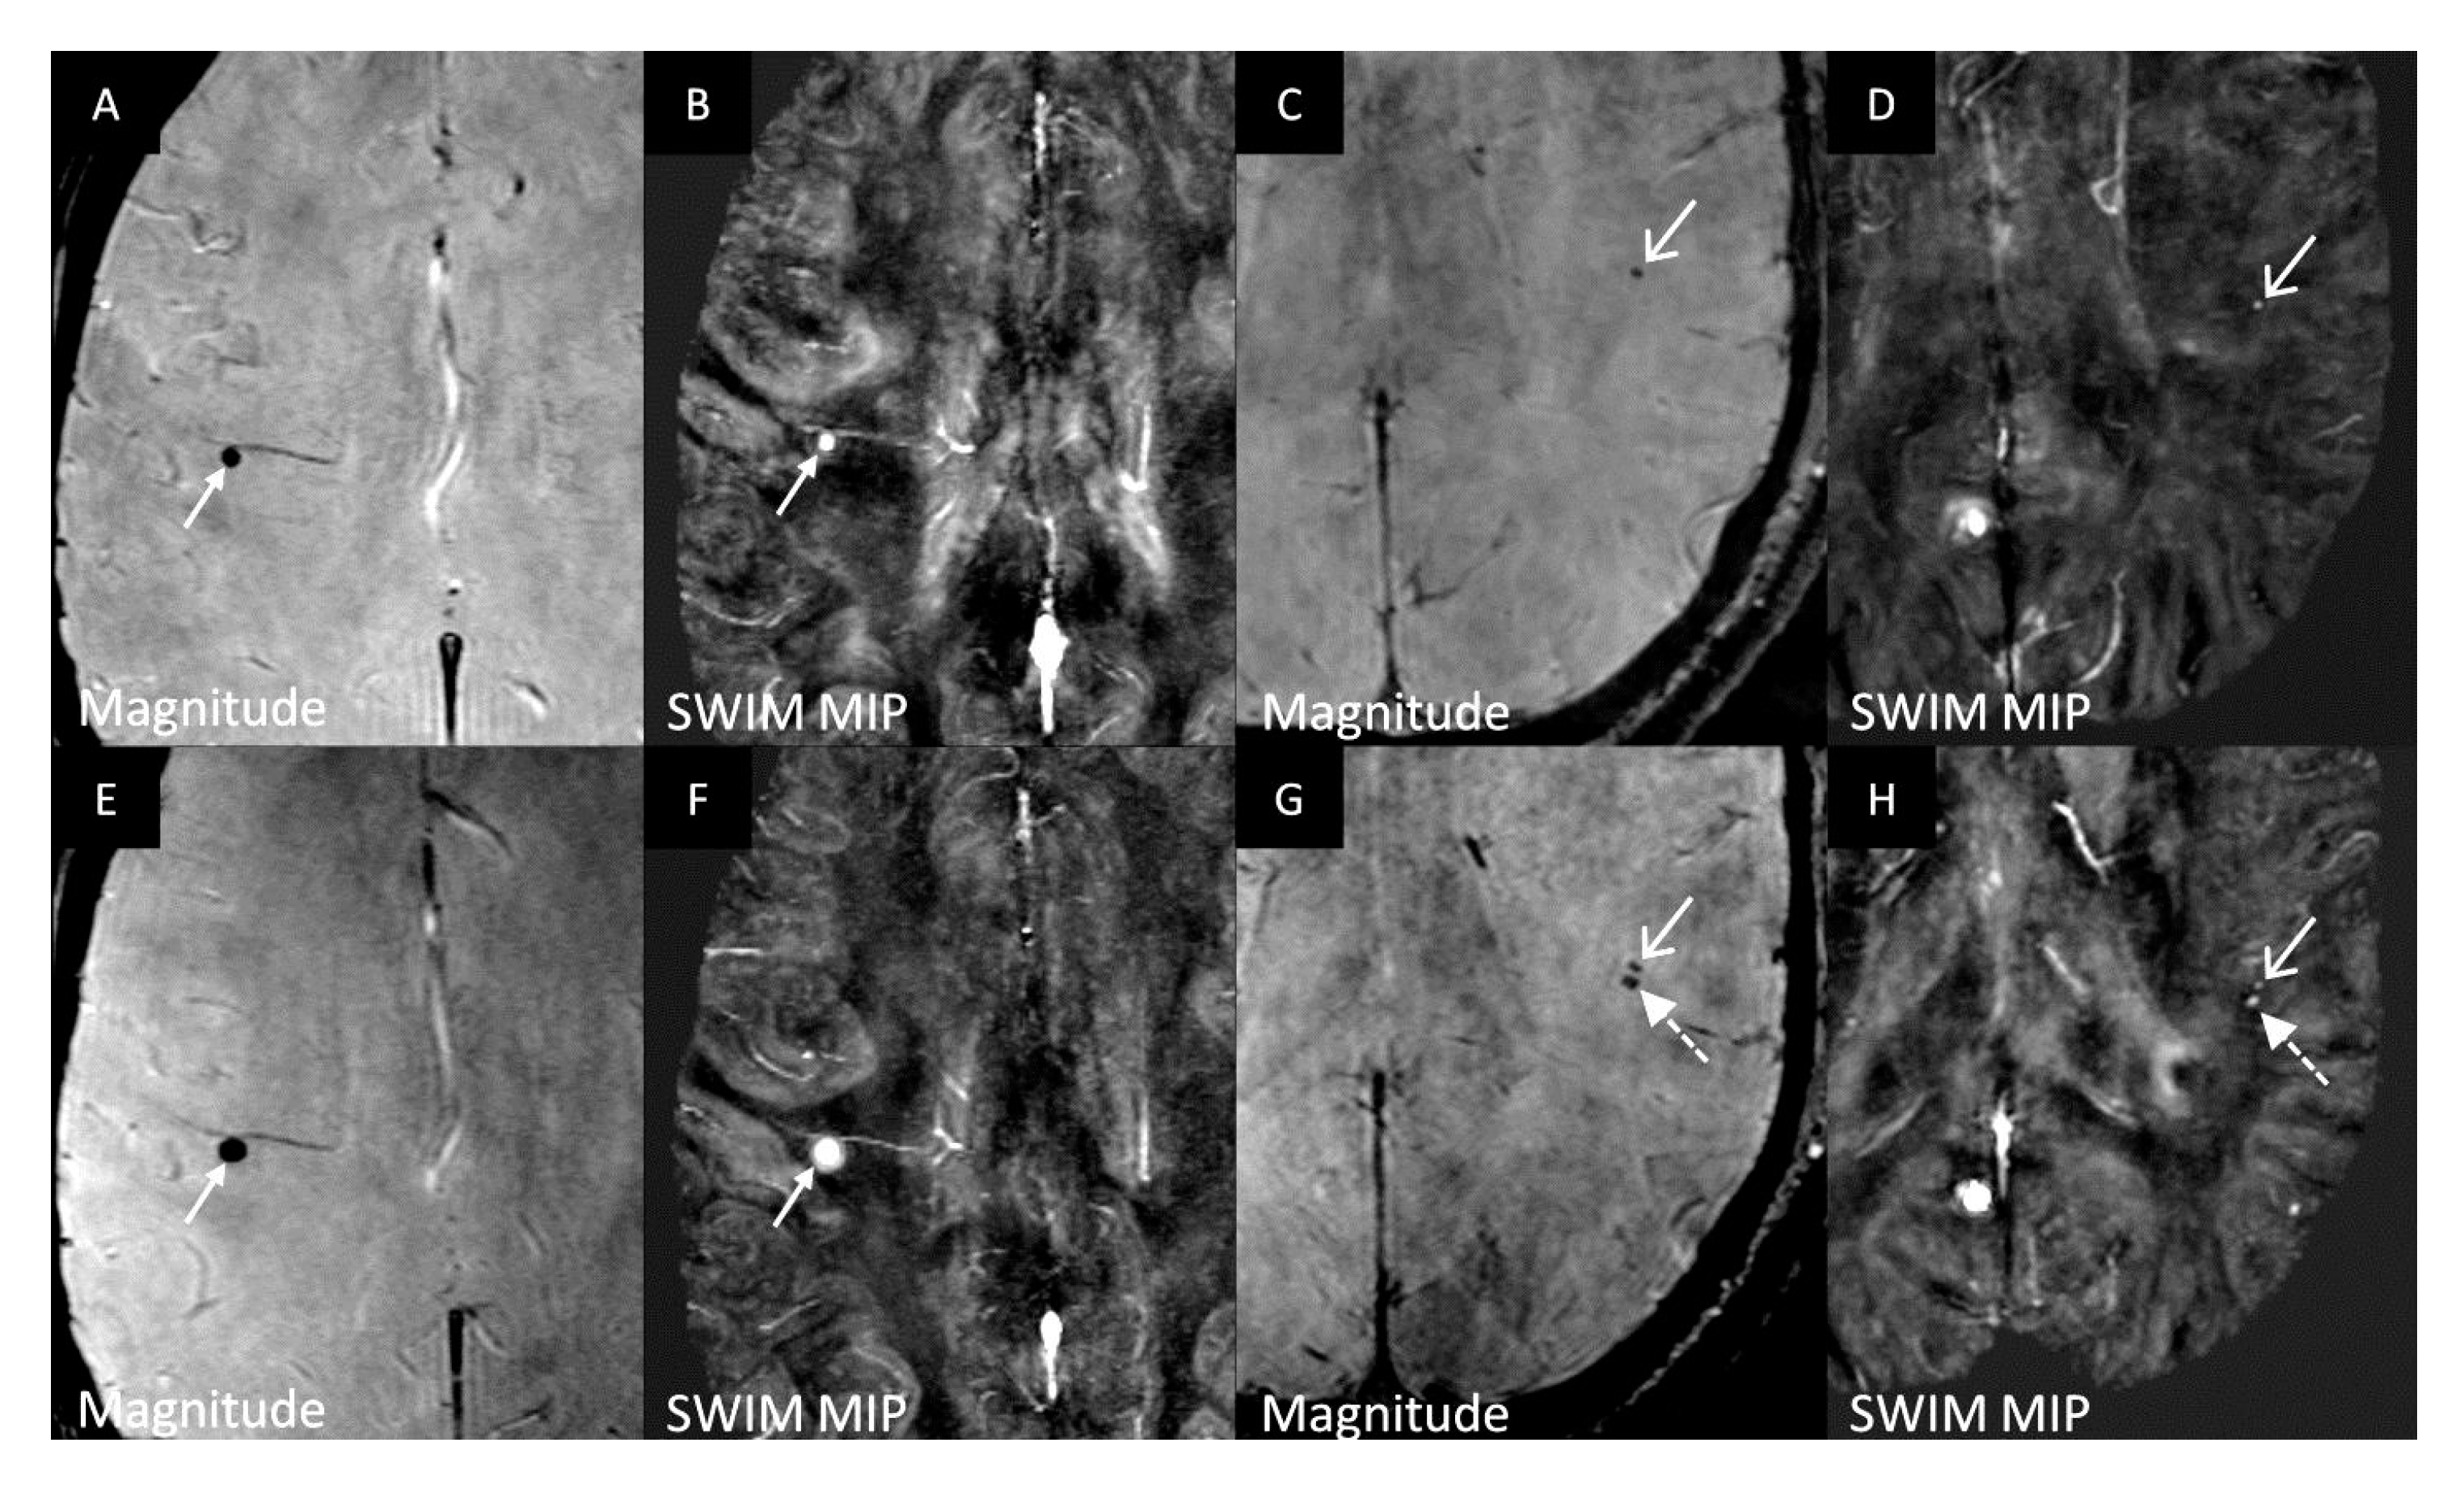

3.3. Longitudinal CMB Analysis